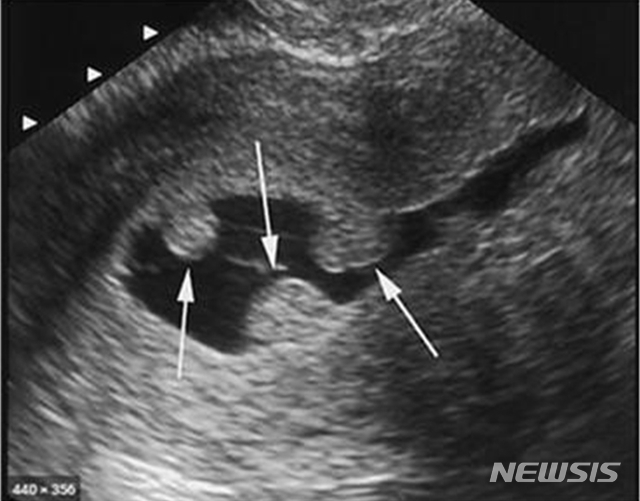

![[익산=뉴시스] =자궁내막용종 초음파 사진.](https://img1.newsis.com/2020/09/14/NISI20200914_0000599892_web.jpg?rnd=20200914104540)

[익산=뉴시스] =자궁내막용종 초음파 사진.

자궁근종과 자궁선근증 외에 만성골반통이나 월경과다를 일으킬 수 있는 질환으로는 자궁내막증, 자궁내막용종이 있다.